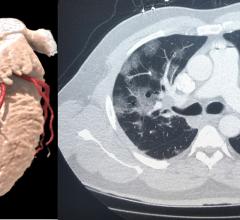

Feature | Computed Tomography (CT)

July 28, 2020 — The use of cardiovascular computed tomography angiography (CCTA) is one of the areas that has seen a…

There has been tremendous growth in the field of cardiovascular computed tomography (CT) in the past two decades, with…